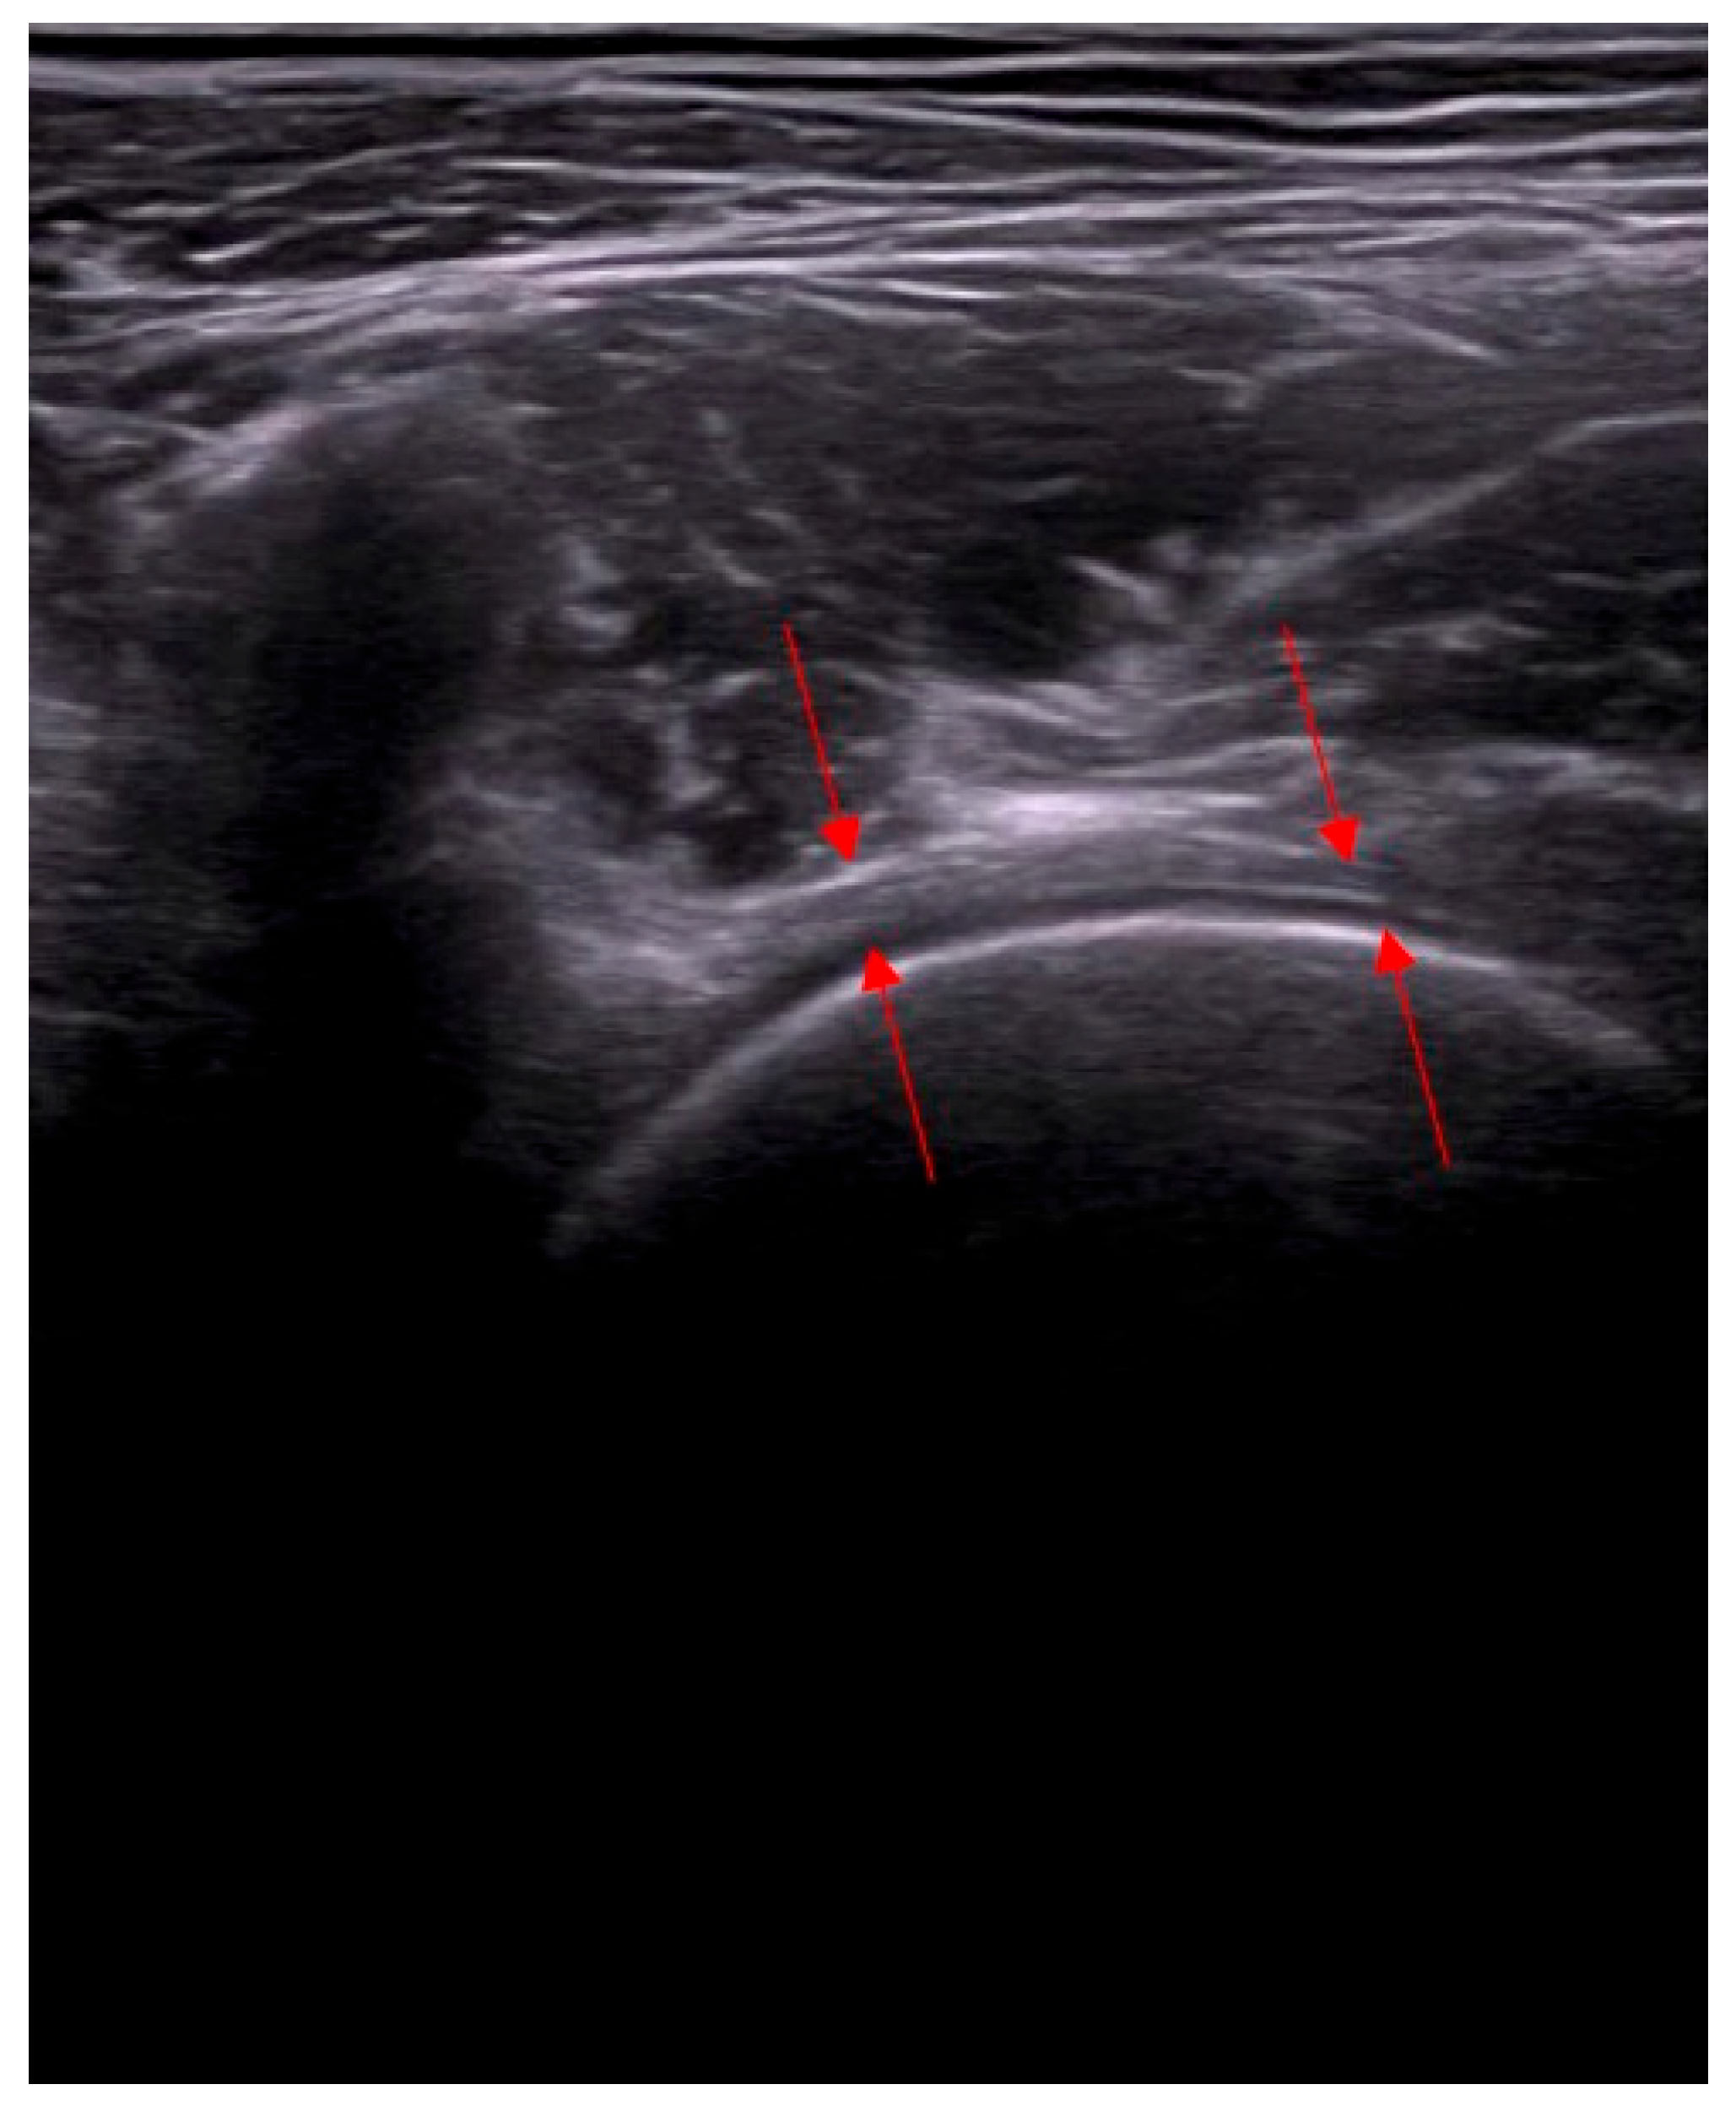

- Assessment of capsular adhesion thickness—ultrasonographic evaluation was performed with the probe positioned transversely, allowing for precise visualization of adhesions. The most common location of adhesions was in the anterolateral complex, with less frequent occurrences in the medial complex.

- Number and distribution of surgical portals—capsulotomy was performed using at least two portals, and in some cases, three or four, depending on the adhesion locations. Standardly, two access points were located in the anterolateral compartment—medially and laterally to the iliopsoas tendon.

- Anterior capsulotomy location—the procedure could include a capsulotomy at the equator of the femoral head in the transverse ultrasound view. Optional additional approaches included a medial approach relative to the neurovascular bundle.